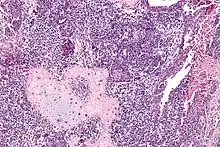

Carcinosarome utérin. HE, x250

Invasion du myomètre par un carcinosarcome utérin avec différenciation rhabdomyosarcomateuse. HE, x400